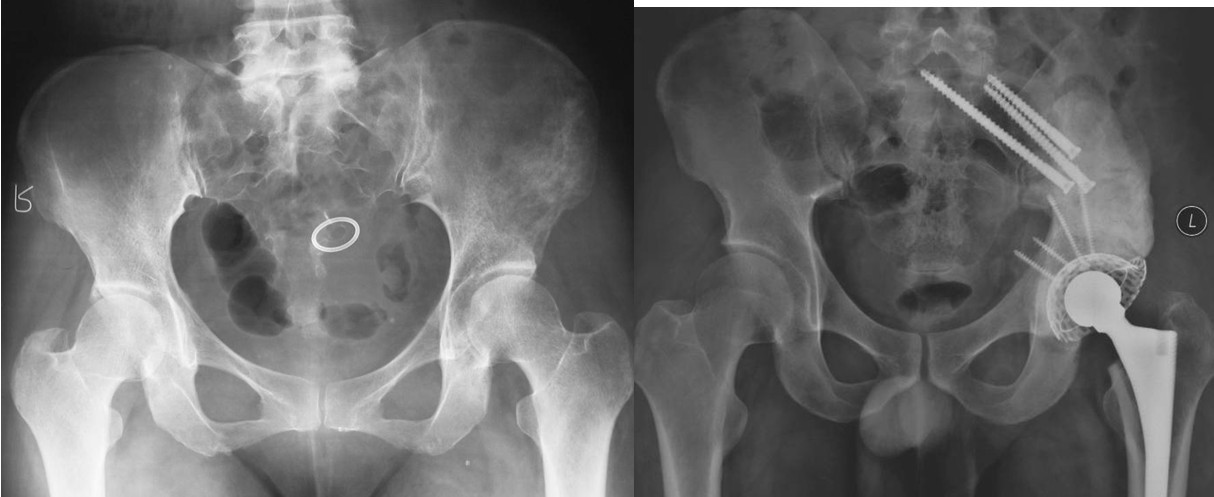

本组病例中不同部位髋臼转移癌的手术方式(图1):I型:髋臼下壁骨破坏、上壁及内、外侧壁完整, 采用肿瘤刮除、普通水泥型全髋置换术。II型:髋臼内、外侧壁破坏,上壁骨质完整, 采用带翼网杯+水泥型全髋置换术。 III型:髋臼上壁及内、外侧壁均破坏,采用肿瘤刮除后、骨水泥填充髋臼上壁骨缺损,带翼网杯+水泥型全髋或组合式人工半骨盆。IV型:孤立性骨盆转移, 以治愈为目的, 采用肿瘤整块切除,组合式人工半盆置换术。

当全髋关节置换用于髋臼转移癌的手术时,需要根据骨破坏的程度、股骨头移位情况采取与常规髋关节置换不同的技术和器械。多数情况下,髋臼部分采用骨水泥固定。如果骨破坏较小,股骨头移位不明显,应用普通骨水泥型髋臼可取得良好效果。如果髋臼周围骨质因转移瘤或放疗后骨坏死大范围破坏,在安装髋臼假体时就需要特殊技术。因为残留的骨质难以防止髋臼组件的移位和松动,所以普通的全髋置换难以成功。骨水泥可以抵抗压力,但不能抵抗剪切应力。用骨水泥来连接大范围的骨缺损并固定髋臼部件的失败率较高。如将髋臼组件安装在高于正常、直接与残存髂骨接触的位置,也容易导致重建失败。股骨部分的假体可以采用常规水泥型全髋置换柄。术前应对整个股骨全长进行X线及骨扫描检查。1981年Harrington根据肿瘤的部位、骨破坏的程度,以及稳定固定的特殊技术要求对髋臼转移癌缺损进行了分类(1)。

Ⅰ型:髋臼外侧皮质,上方及内侧壁完好,髋臼下及前后方破坏缺损。可以采用骨水泥固定的普通全髋置换术以达到长期牢固固定。手术入路一般采用后外侧入路,不需要大转子截骨,可在髋臼深部放置金属网以加强骨水泥的固定效果,阻挡股骨头向内移位。术后第一天病人即可在耐受范围内下地活动并完全负重。

Ⅱ型:髋臼内侧壁缺损,而周边骨质完好。采用普通髋臼会导致假体及骨水泥早期向内侧移位。对于这种情况,应采用特殊设计的带翼髋臼网杯将应力引至髋臼缘。安装时在保持髋臼假体正确解剖位置的同时需注意将网杯的翼放置在完整的髋臼缘,因为部分髋臼边缘可能存在破坏。可以采用后外侧入路,通常无需大转子截骨,尽量使用长颈人工头,以防止粗隆部撞击网杯延伸缘。股骨粗隆部,股骨干有潜在骨折时,应使用长柄髓内针的人工股骨头。术后第一天病人即可下地负重活动。

Ⅲ型:髋臼内壁、顶部及外侧壁均破坏。仅使用带翼网杯的全髋假体是不够的。在这种情况下,需要在骨盆缺损处放置数根斯氏针以便于将位于解剖位置的髋臼假体所承受的应力传导至脊柱(1-3)。在大多数髋臼周围破坏广泛的病例,需要采用扩大的髂股骨切口入路,以便于探查骨盆内外侧区域。在显露清楚后,自髋臼缺损处沿残留的正常髂骨向骶髂关节方向钻入2-3根斯氏针,并越过关节达到骶骨。应采用较粗的斯氏针,术中还需要X线监测以保证斯氏针的位置。在钻入斯氏针的同时,应用手指触摸坐骨切迹,以保证斯氏针的方向,防止其穿入骨盆内壁。当髋臼缺损较大时,还可以自前部髂嵴向前柱的耻骨及后柱的坐骨钻入更多的斯氏针做进一步的加强。在髋臼假体顶部切断斯氏针,并安装带翼网杯,在髋臼深部可以用金属钛网加强骨水泥固定。术后病人可全部负重行走,但需置患肢外展中立位约4周时间以防止脱位。也有采用马鞍式假体置换的报道, Benevenia等对20例髋臼III型转移瘤患者进行了马鞍假体置换,术后MSTS 93评分平均16.6分,多数病人可以扶拐行走(5)。对于髋臼上壁及内、外侧壁均破坏的HarringtonIII型患者,本组病例中,有7例患者采用了肿瘤刮除后、于骶髂关节处植入3-4枚斯氏针, 骨水泥填充髋臼上壁骨缺损,水泥型全髋重建髋关节。其中,有2例患者出现下地后髋部痛疼,负重时髋部不稳定。考虑为负重时骶骨内斯氏针承受较大剪力, 出现髋关节不稳。因此,在本组病例中,我们对4例Ⅲ型患者实施了整块切除、可调式人工半骨盆置换术。术后6周患者可以扶拐下地行走。平均MSTS93评分为23.3分。

图1, 髋臼转移癌的分型示意图(北京大学人民医院)

图2,女,31岁,乳腺癌髋臼转移, Harrington I型

图3,女,55岁,肺癌髋臼转移, Harrington II型

图4,女,52岁,乳腺癌髋臼转移, Harrington III型

图5,男,69岁,肾癌髋臼转移, Harrington IV型